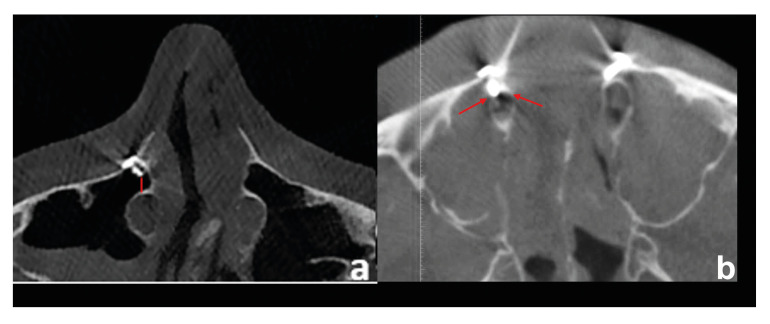

Material and methods: The authors conducted a retrospective cohort study consisting of patients who underwent Le Fort I osteotomies between 2017 and 2021 in the Erciyes University Faculty of Dentistry. The primary predictor variables were the distance of the nasolacrimal canal to the outer cortex of the maxilla and the nasal floor, as well as the superior-inferior level of the superiorly positioned screw inserted in the maxilla aperture region relative to the nasolacrimal canal. The outcome variable was the presence of a nasolacrimal duct injury. Mann Whitney U test was used for quantitative variables between the two groups. A Pearson chi-squared analysis was used to compare categorical data. A p-value <0.05 was considered statistically significant.

Results: A total of 290 nasolacrimal canals were evaluated in 145 patients, 87 females, and 58 males. The mean age was 23.47± 6.67. There was a statistically significant relationship between screw level and nasolacrimal canal perforation (p<0,001). The distance between the most anterior border of the nasolacrimal canal and the outer cortical of the maxilla was significantly less in the perforation group (p<0,001). The fixation screw was significantly closer to the nasolacrimal canal in the perforation group (p<0,001).

Conclusions: In Le Fort I surgery, nasolacrimal duct injury may occur during screw fixation to the aperture region. Superiorly positioned fixation screws in the aperture region may damage the nasolacrimal canal. In patients where the nasolacrimal canal is close to the outer cortex, care should be taken when applying the fixation screws to the aperture region to avoid damaging the canal.